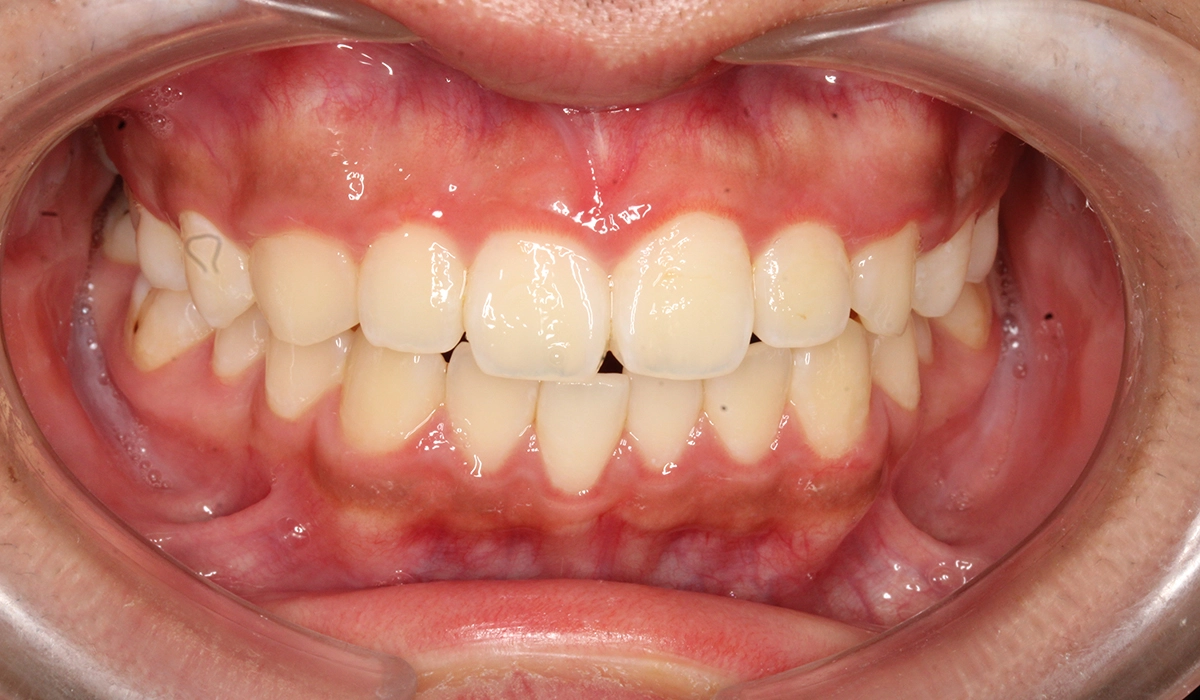

術後:正面